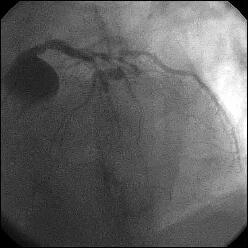

�Ǘ��72�Ώ����Brisk factor��HT, HL, DM�ł��B

��2�T�ԑO�̔��ǂƎv����Recent MI�ł��BLAD#7: total��Tristar3.0�~18?�����

�܂����B

����LCx ostium: 75%�ł��B������PCI���悤�Ǝv���̂ł����A�ǂ̂悤��strategy

�����ł��B

�Y�t���ꂽ�A���W�I�̂����A�ŏ��̂��̂�q������ƁALCx�������ɂ���Ȃ�́g��

�肵��h�́A�����悤�ł��B

DCA����������̎�i�ł����ACB���X�e���g�ł����܂�Ȃ��̂ł͂Ȃ��ł��傤

���B

�������A�ł��邾���X�e���g�̃T�C�Y��傫���������̂ŁAIVUS���������ł����A

LAD��������plaque shift���N���A�ň�LMT�ł�kissing�̉\��������̂ŁA

�K�C�h��7Fr�iradial���ׂ����TFI�Łj�A�X�e���g�A�����݂ɍۂ��ẮA

�O�̂��߁ALMT��LAD��protect wire�A�Ƃ������Ǝv���܂��B